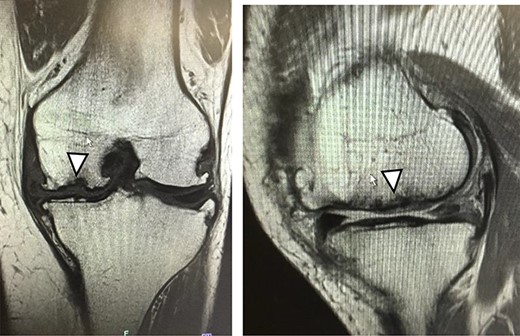

There were cartilage defects (arrowhead) in the medial femoral condyle and trochlea of the left knee (a, b).

Articular cartilage injury was shown in the medial femoral condyle (arrowhead) (2.5 × 3.5 cm; Outerbridge classification, Grade III) and trochlea (arrowhead) (1.3 × 1.7 cm; Outerbridge classification, Grade III) (a, b).

A 42-year-old female (BMI, 27.4 kg/m2) presented with 2 years of left knee medial joint pain. Active range of motion (ROM) in the left knee was from 0 to 140 degrees with no extension lag. Preoperative Tegner scores, Lysholm scores and Knee Injury and Osteoarthritis Outcome (KOOS) scores are shown in Table 1. Preoperative radiographs of the left knee joint showed mild medial osteoarthritis (OA) of the knee and hip–knee–ankle (HKA) angle of 1.5-degree varus. 1.5-Tesla MRI was performed on unit (Toshiba, Kawasaki, Japan) was used with an extremity surface coil. Proton density images were obtained using the fast spin-echo technique. A modified magnetic resonance observation of cartilage repair tissue (MOCART) system was used for the quantitative evaluation of MRI findings of the cartilage injury [15–17]. MRI showed cartilage injury of the medial femoral condyle (MFC) and trochlea of the left knee (Fig. 1).